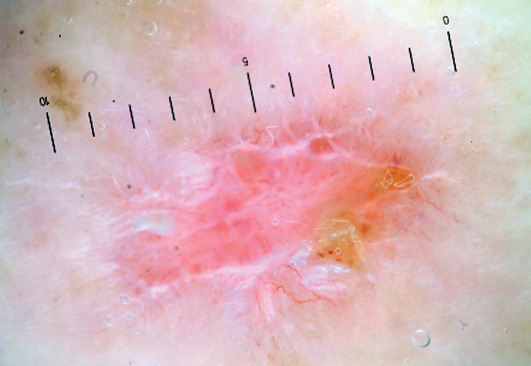

Дерматоскопические изображения для последующего анализа были получены с помощью дерматоскопов DermLite DL3N, Heine DELTA 20(T), адаптеров и фотоаппаратов Nikon 1 J1, Canon 750D. Фотографии сделаны в поляризованном режиме дерматоскопа с использованием ультразвукового геля в качестве иммерсии.

- 26 пациентов с 28 элементами болезни Боуэна, диагноз во всех случаях подтвержден патоморфологическим исследованием;